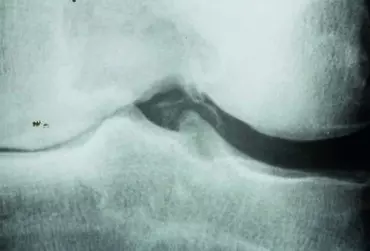

Rola rehabilitacji w leczeniu zachowawczym chondromalacji rzepki

Staw kolanowy pełni funkcję amortyzatora dla układu ruchu człowieka. Nadmierne obciążanie kolan może doprowadzić do zbyt szybkiego zużycia, co może w dalszej części nieść ryzyko innych problemów. Jednym z nich jest chondromalacja rzepki.